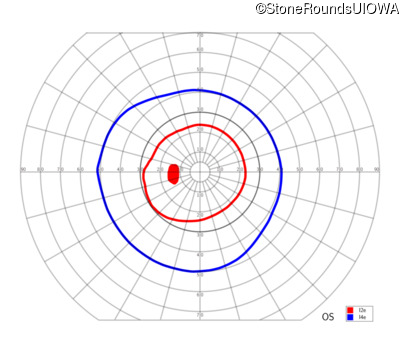

XL Retinoschisis (IIIB1)

XL Retinoschisis (IIIB1)

This 6 year old boy first experienced difficulty reading and seeing the blackboard at age 5.